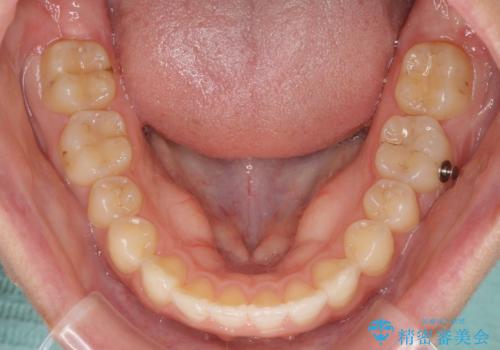

インビザライン矯正で前歯のデコボコを改善

- 前歯のデコボコを気にして来院された患者様です。

目立たないことを最優先にしたいとのことで、デコボコは軽度であったことから、インビザラインにて矯正治療を行うこととしました。

骨格的に下顎骨が左にずれており、上下の正中一致は困難ではありましたが、IPR(歯と歯の間を削る)や後方への移動など組み合わせて、できる限り改善しました。

インビザラインはマウスピースを外している時間が長いと、長期間使用しても前歯のデコボコはあまり改善されません。こちらの患者様は治療期間が長くなり、装着時間が短くなってしまったことで、気になる部分の改善により長期間を要するようになってしまいました。